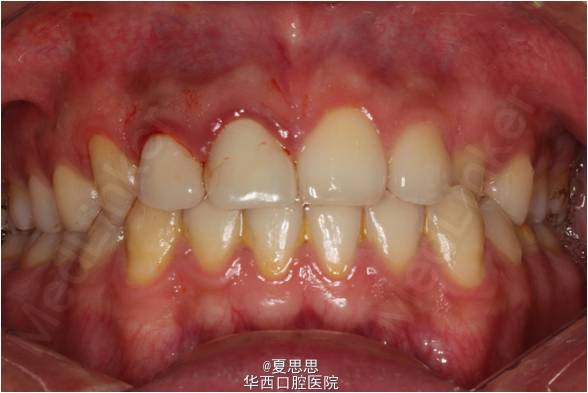

现病史:患者自述八年前门牙磕断,在老家诊所修复,今假牙略有松动并发黑,影响美观,因此要求治疗。

检查:21 自凝树脂桩核修复,树脂冠略有松动,叩诊无明显不适,唇侧牙龈有一陈旧性瘘管。

诊断:21不良修复体